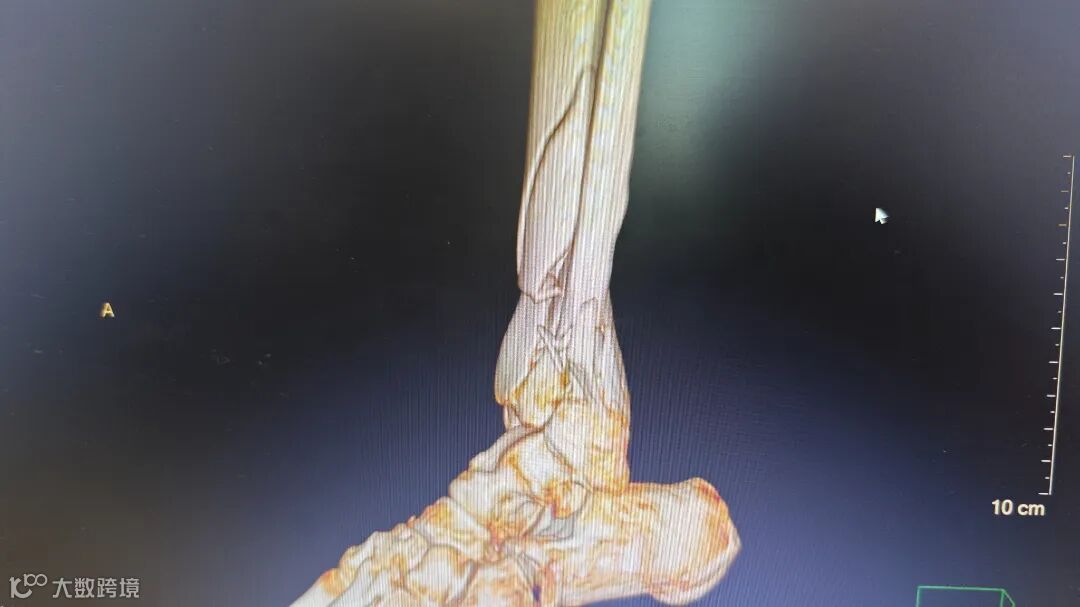

术后腿部影像

胸外科专家会诊后确认,患者肋骨骨折无明显位移,决定采用胸带固定配合卧床静养的保守治疗方案。针对更为复杂的小腿骨折,骨科团队在5月4日由张均锦主刀,曹桂青、陆仕邦医师协助下实施了精准复位手术。术中使用接骨板进行内固定后,X光显示骨折端对位良好,术后第三天患者已能进行简单的足部活动。